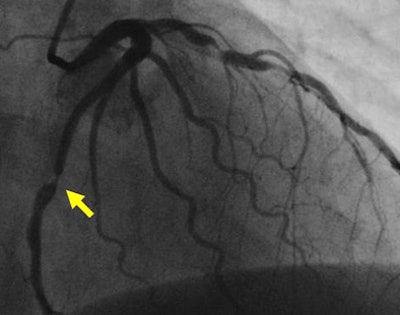

| Stenosis in left anterior descending artery detected at CT angiography (above) is confirmed at angiography (below). Images courtesy of Dr. Matthew Budoff. |